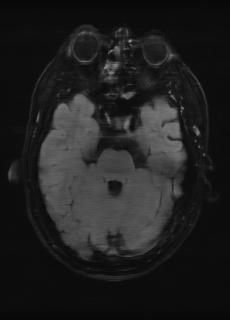

As we observe from the right image in Fig. 2, our BRM, both from MIMO and SISO settings, predicts the performance of dedicated models with a high correlation. We further choose the best three , and perform the last stage of fine-tuning accordingly to (6). A visual evaluation on real data is shown in Fig. 3. For simulated data, please refer to the Supplemental Material section.

Base on the best performing , we perceive that among , , and FLAIR, the results are best when is sampled the most. We suggest that this makes intuitive sense as images provide the best contrast out of the three sequences, which can compensate for the details lost in other images. The same observation can be made on the simulated data, where both and FLAIR show good contrast. When the time setting is changed to non-uniformity, we can see that our search for the best sampling strategy reflects the change. is sampled more as a result of faster acquisition time, while is still sufficiently sampled.

(a) 34.38/0.9371

(a) 34.38/0.9371

|

(b) 42.42/0.9883

(b) 42.42/0.9883

|

(c) 44.60/0.9920

(c) 44.60/0.9920

|

(d) 45.50/0.9940

(d) 45.50/0.9940

|

(e) PSNR/SSIM

(e) PSNR/SSIM

|

|

(f) 29.74/0.8903

(f) 29.74/0.8903

|

(g) 36.25/0.9734

(g) 36.25/0.9734

|

(h) 36.42/0.9752

(h) 36.42/0.9752

|

(i) 37.70/0.9832

(i) 37.70/0.9832

|

(j) PSNR/SSIM

(j) PSNR/SSIM

|

|

(k) 39.89/0.9311

(k) 39.89/0.9311

|

(l) 43.94/0.9864

(l) 43.94/0.9864

|

(m) 44.74/0.9883

(m) 44.74/0.9883

|

(n) 45.49/0.9894

(n) 45.49/0.9894

|

(o) PSNR/SSIM

(o) PSNR/SSIM

|